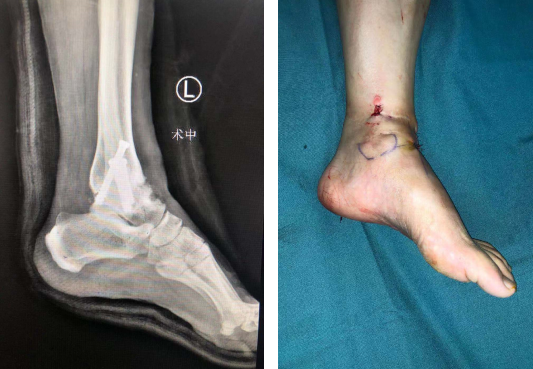

术后X线(左图)术后(右图)

石荣剑副院长周吉医生手术团队为患者进行了手术。术中,医生操作关节镜进入踝关节腔内探查,刨削器清理肉芽组织、充血滑膜组织,清理踝关节各软骨面,术中取出两块增生骨赘游离体,这是导致患者关节疼痛的一个因素;随后,在踝关节间隙填充人工异体骨,在机器人精准定位下分别从胫骨近端、腓骨近端交叉钉入3枚克氏针作为导针,沿导针钉入空心螺钉3枚,C型臂透视见踝关节融合位置良好,内固定在位。手术顺利结束。